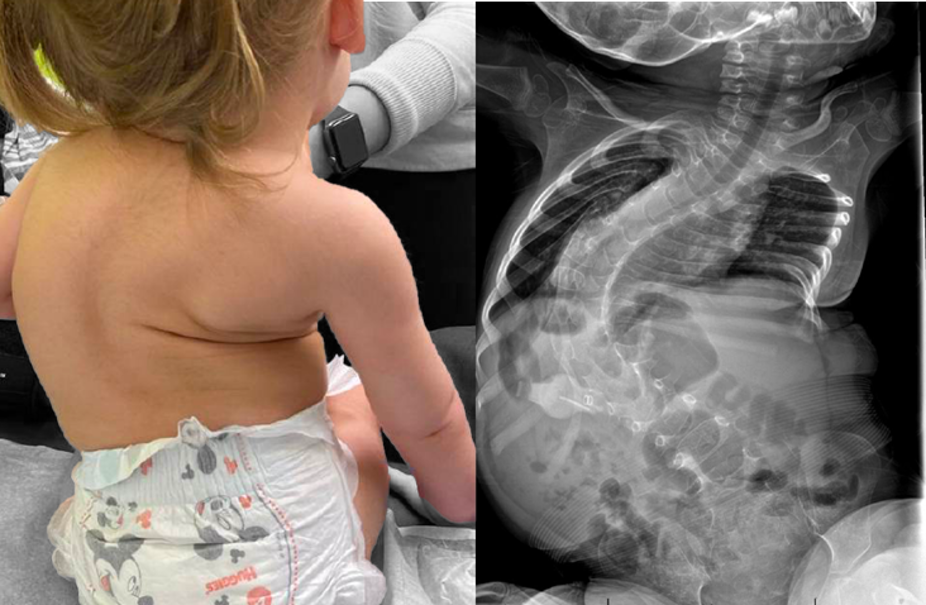

Spinal muscula atrophy causes muscle wasting and loss of control, usually starting in infancy. Orthopedia/Codman Group, CC BY-NC-SA

This causes the loss of muscular control that is the characteristic symptom of the disease – where, for example, babies with the most common spinal muscular atrophy, type 1, usually fail to reach the developmental milestones such as actively rolling, sitting or crawling that most of us, as parents, take for granted. Other, milder types of the disease appear later in childhood (types 2 and 3) or in young adults (type 4), and result in progressive loss of muscle function. Some adults with the disease, such as Michaela Hollywood, work to raise awareness of it.

To get Spinraza into motor neurons, the drug needs to be injected directly into the spinal column by lumbar puncture. Unpleasant at the best of times, this can be particularly challenging in older children and adults living with the disease, as spinal curvature is common. It also needs to be administered regularly: up to six injections in the first year of treatment at a cost of £75,000 per injection, and three each year after that.